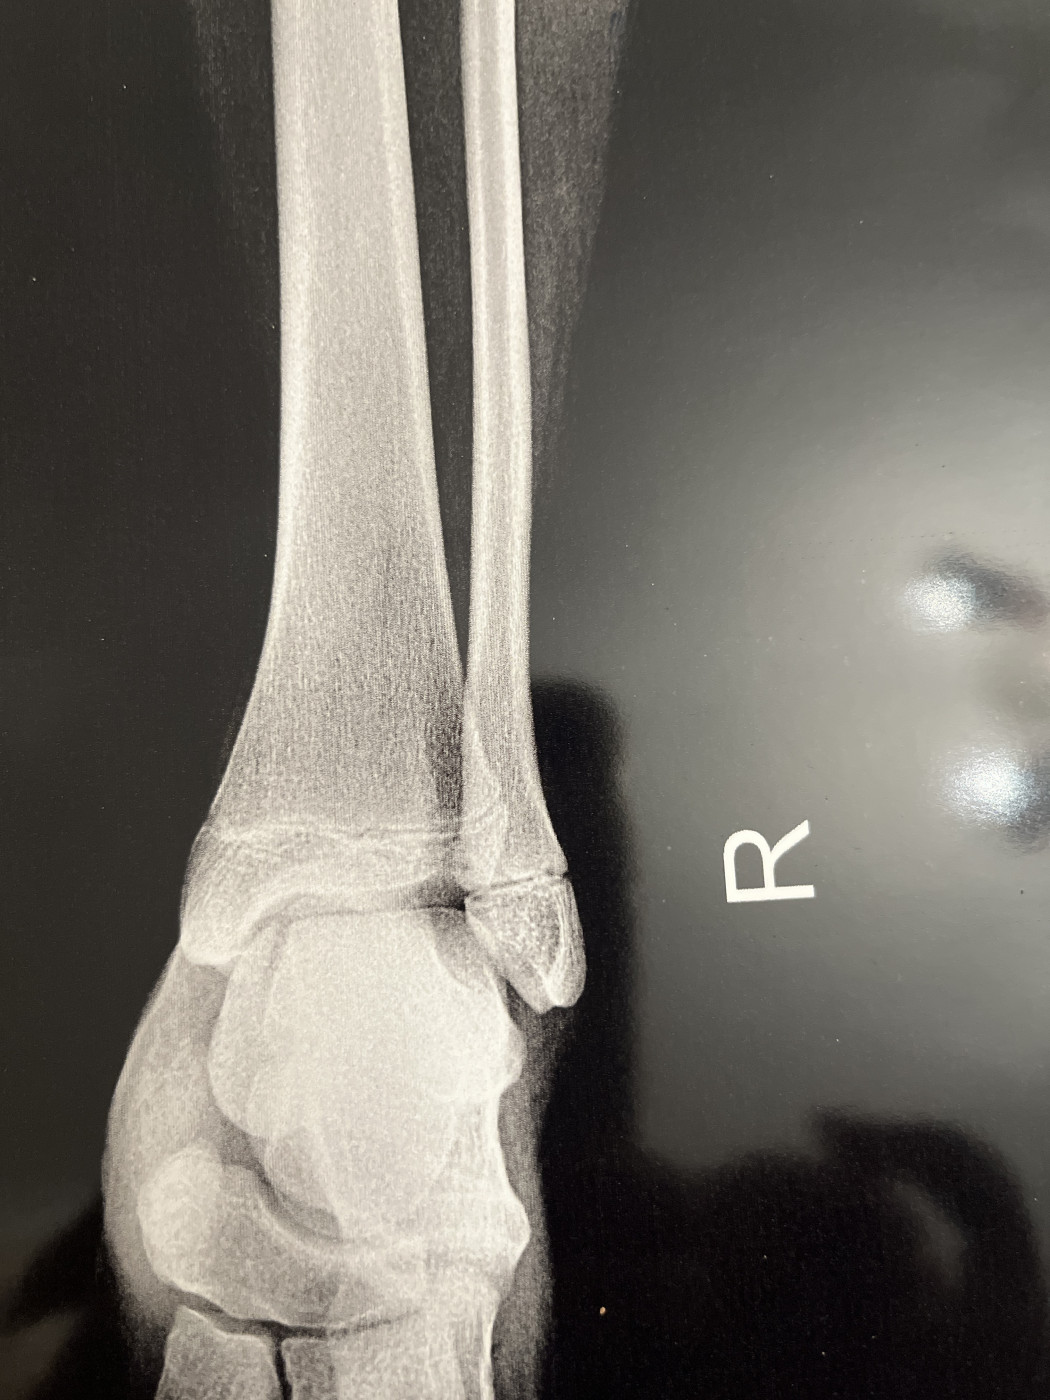

Есть ли перелом?   2 ответа

Ребенок перепрыгивал ливневую и оступился упал на бок, опухла в районе косточки ладыжки. В травматологии сделали снимок, сказали трещина, нужно носить ортез 3 недели. Переживаю, может нужен гипс и там серьезный перелом?